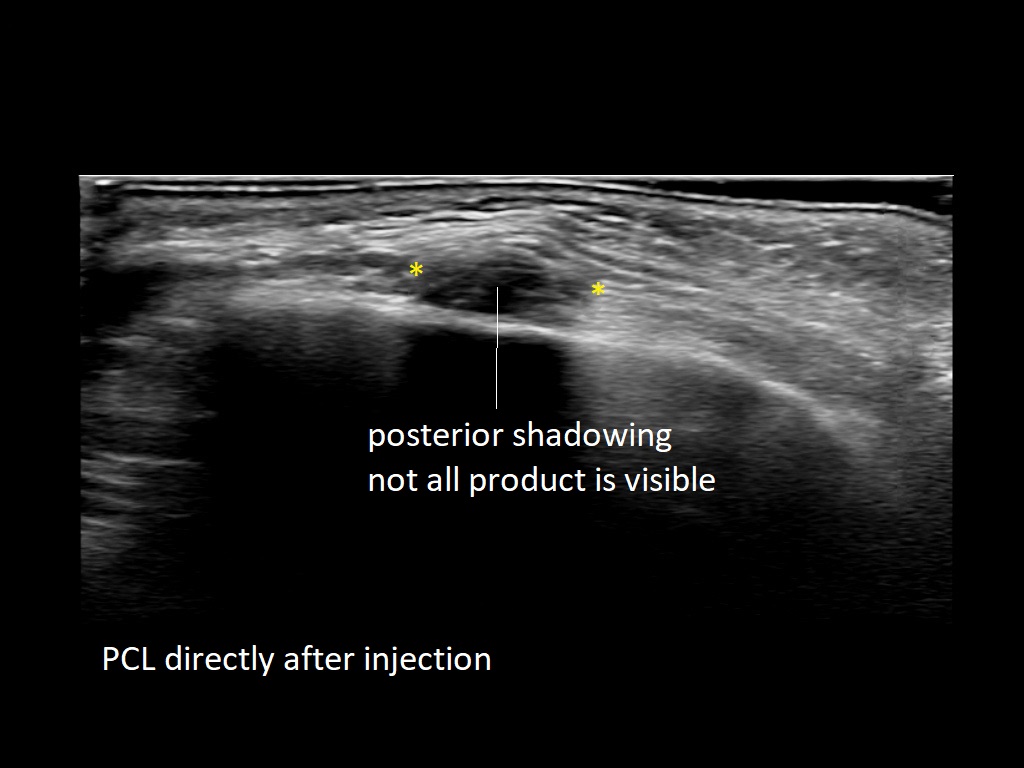

PCL 0

PCL 1a

PCL 2a

PCL 3a

PCL 3b e

PCL 4a

PCL 4b e

PCL 5a

PCL 5b e